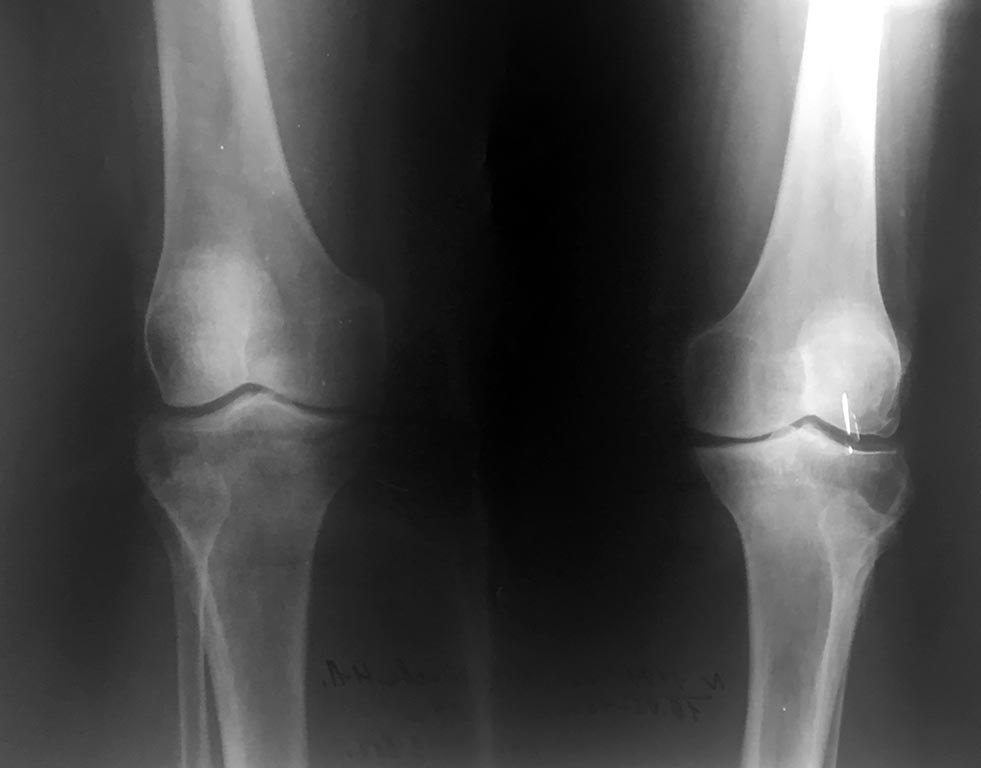

Пациентка 67 лет. Страдает двусторонним гонартрозом 2 ст. В течении последнего года усилился и постоянно беспокоит болевой синдром.

Варусная деформация выражено умеренно. Объём движений 180-85 гр. Без значимой сопутствующей соматической патологии.Консервативное лечение с малым эффектом.

Какие варианты лечения в этом случае приемлемы?Возможна ли в данном случая корригирующая остеотомия ББК ? или показано эндопротезирование?одномыщелковое?

1. Снимки в одной проекции!! И с неправильной укладкой— ротация кнаружи! Создаётся впечатление латерализации надколенника. Возможно ложное.

2. Сделайте снимки стоя, и суставная щелью скорее всего, окажется никакой, и Вы поймёте, что следует сделать.

3. Боковая рентгенограмма даст возможность оценить пателло— феморальный сустав. И не только.